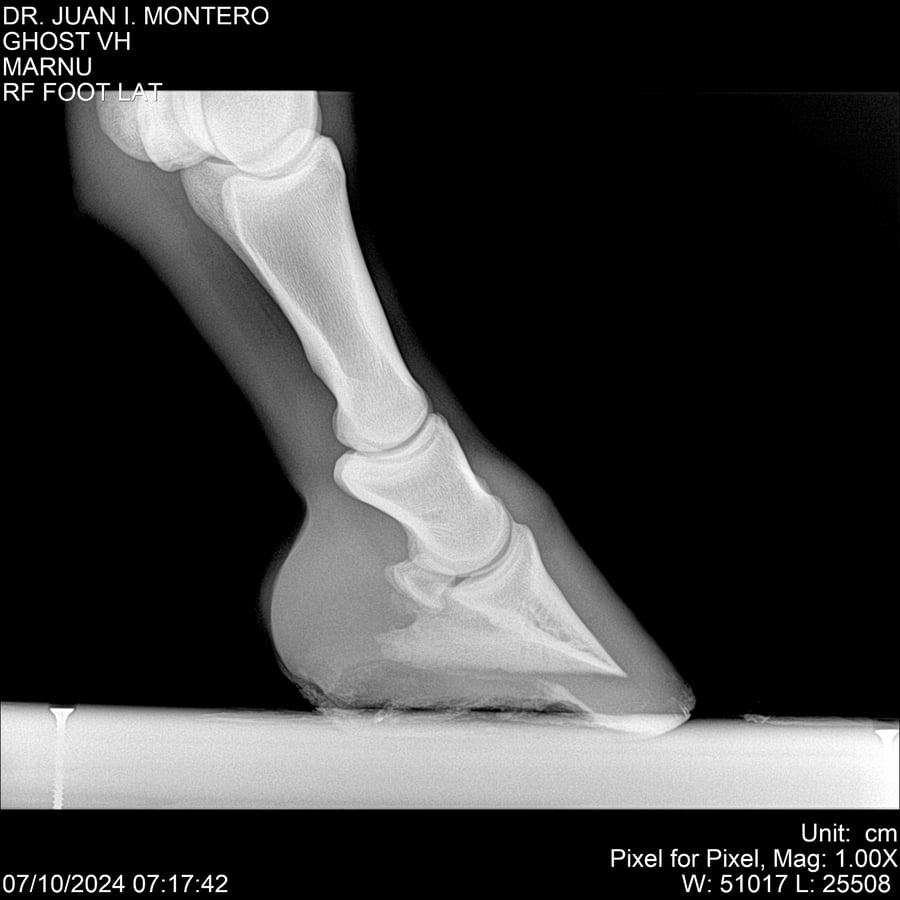

LOTE 15, GHOST VH 🔥 🔥 🔥 Lote Anterior Volver al remate Lote Siguiente Ficha Contacto Montevideo - Ficha del Lote Identificador: #282525 Categoría: Yeguarizos Montevideo - 69 Visualizaciones ClicData Contacto Empresa: Abelenda N. R., Walter Hugo Nombre*: Teléfono* : E-mail* : Mensaje Enviar Registrese gratis Este contenido Exclusivo está disponible sólo para usuarios registrados Ingresar